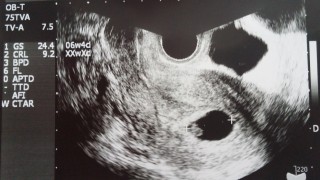

赤ちゃんは7ミリでした。先生「赤ちゃん成長してるね~」しか言わないので 「心拍は。。。?」って恐る恐る聞いてみたら「あれ?見えなかった?ちゃんと動いてるよ~」って拡大して見せてくれました。小さい赤ちゃん、一生懸命生きてました。過去に流産を経験してるので今日まですごく不安でしたが、心拍確認出来て本当に良かった。

1人目GS15.1mmCRL4.8mm、

2人目GS17.4mmCRL8.4mmとのことです。どっちがどっちなのかな?双子ちゃんの心拍がチカチカしてるのを見て、感動で涙目になりました!